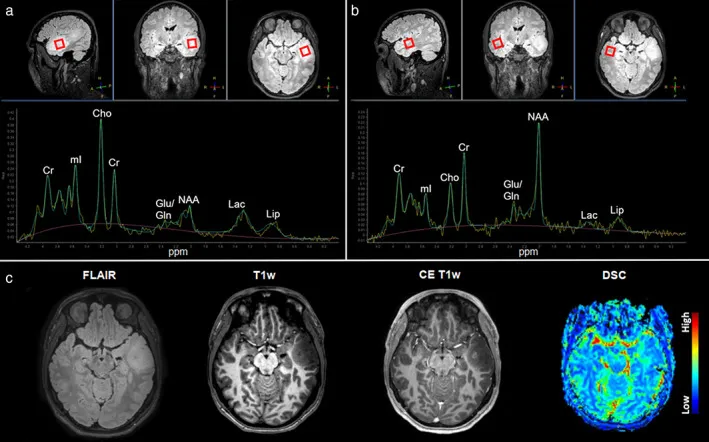

胶质母细胞瘤MRS表现显示典型代谢特征。

此外,研究表明MRS可根据相应的NAA/Cho和NAA/Cr比值来区分胶质瘤和非胶质瘤病变。而且,MRS可能是一种引导立体定向组织活检的可行手段,因为具有高Cho/NAA比值的肿瘤区域被认为最适合进行组织病理学评估。

MRS在评估肿瘤进展方面的作用也日益受到关注。一项研究显示,在替莫唑胺治疗的患者中,一年内病灶中心Cho浓度的降低与肿瘤体积的缩小相关,这凸显了MRS在监测化疗反应方面的价值。